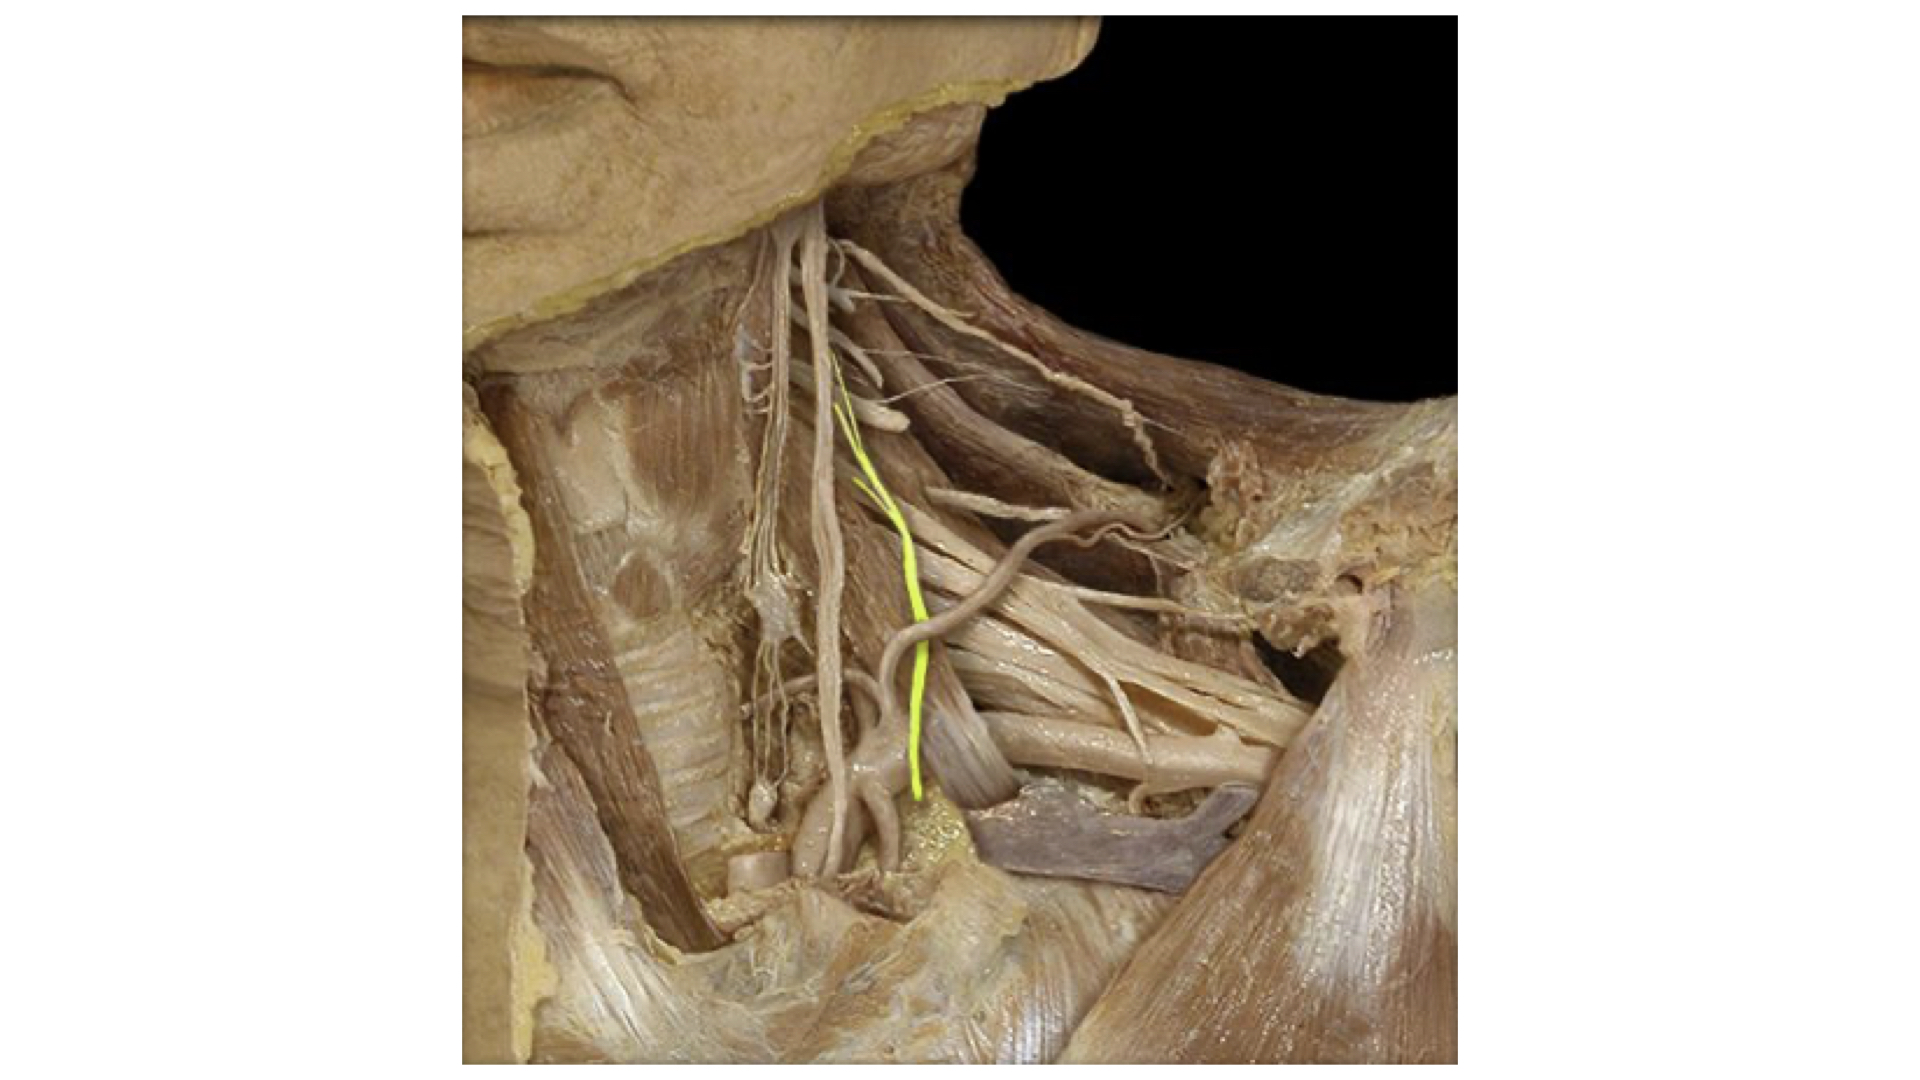

a. Cervical plexus: The major nerve that is formed here is the phrenic nerve. The phrenic innervates the diaphragm and controls breathing.

Cervical Plexus--Phrenic Nerve Highlighted

Cervical Plexus--Phrenic Nerve Highlighted